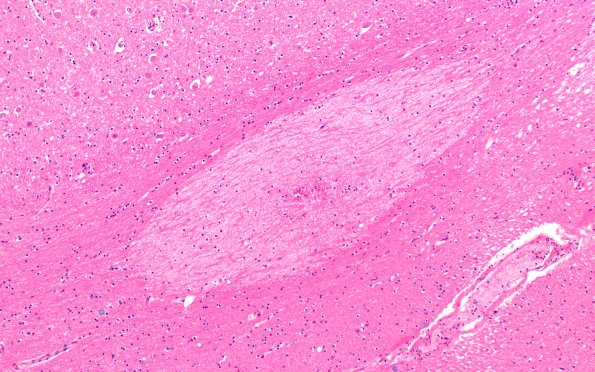

12E2 Fat Embolism (Case 12) N4 10X

There are multiple lesions in the thalamus (12E2-4) (H&E)